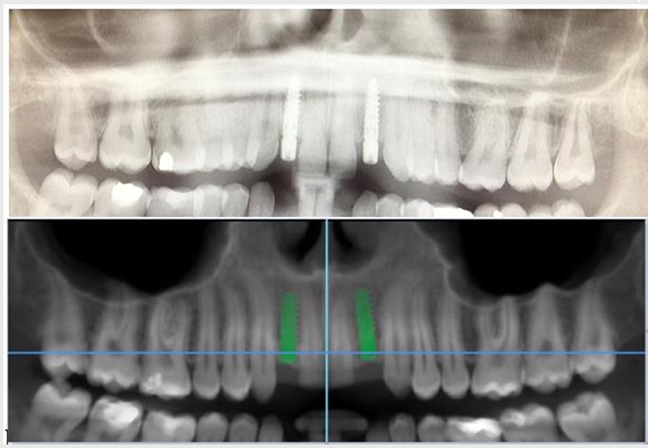

Let's look at a real case: A patient presented with limited mesial-distal space for implant placement. Using Alpha-Bio Tec's guided surgery system, we achieved:

- Perfect implant positioning

- No damage to adjacent tooth roots

- Ideal prosthetic orientation

- Advanced CT scanning protocols (including innovative Dual Scan technology)